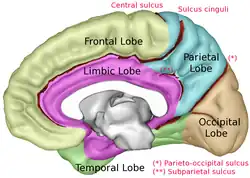

Le lobe limbique est une région arciforme (sous forme d'un arc) du cortex sur la partie médiane de chaque hémisphère cérébral chez les mammifères, constitué de parties du lobe frontal, du pariétal et du lobe temporal. Le terme reste ambigu, certaines définitions incluent le gyrus sous-calleux, l'aire subcalleuse, le gyrus cingulaire, le gyrus para-hippocampique, le gyrus denté, l'hippocampe et le subiculum[1] ; alors que la Terminologia Anatomica fait inclure également le sillon cingulaire, le gyrus cingulaire, l'isthme du gyrus cingulaire, le Gyrus fasciolaire, le gyrus para-hippocampique, le parahippocampique sillon, le gyrus denté, le sillon fimbrodenté , le fimbria de l'hippocampe, le sillon collatéral, et le rhinal sulcus, et omet l'hippocampe.

Lobe limbique (indiqué en rouge) de l'hémisphère cérébral gauche.

Lobe limbique (indiqué en rouge) de l'hémisphère cérébral gauche. Lobe limbique (en orange) de l'hémisphère cérébral gauche.

Lobe limbique (en orange) de l'hémisphère cérébral gauche. Lobe limbique (représentée en violet) de l'hémisphère cérébral droit.

Lobe limbique (représentée en violet) de l'hémisphère cérébral droit. Lobe limbique (représentée en violet) de l'hémisphère cérébral droit.

Lobe limbique (représentée en violet) de l'hémisphère cérébral droit.